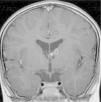

In the 74.3% (26) patients for whom MRIs were available, 76.9% (20) of them had tubers in every cerebral lobe and more than 15 tubers in total, thus presenting high lesion load. Radial migration lines were observed in 96.2% (25) of the patients (Fig. 1). Subependymal nodules were found in 84.6% (22), most of them calcified, and 3 of them enhancing (Fig. 2). Infratentorial tubers were found in 23.1% (6) of the patients. Cyst-like tubers were present in 7 (26.9%) patients, with juxtacortical location in 6, and infratentorial location in 1 (Fig. 3). There was one probable case of giant cell astrocytoma, around the foramen of Monro, measuring less than 1cm, without hydrocephalus (Fig. 4). Focal atrophy was not found in any of the patients.

We reviewed the MR studies of all patients with an identified TCS2 mutation except one, and found a high lesion load in all of them. One of the 5 patients with a TSC1 mutation had a high lesion load. Of the 5 cases associated with refractory epilepsy, 2 had cyst-like tubers.

Tubers with subcortical cysts were defined as lesions with cerebrospinal fluid signal characteristics on MRI bordered by a hyperintense rim in T2 scans. Tubers and Calcified tubers and subependymal nodules showed low signal in T2 and T2* scans. Since the density of tubers in brain parenchyma is suggested as the best marker of severity of epilepsy and cognitive function1, we performed a qualitative assessment of brain tubers density by estimating the frequency of tubers in each cerebral lobe. The density of tubers reflects brain lesion load, obtained by evaluation of the total number of tubers and involvement of each brain lobe by tubers. High brain lesion load was considered if all cerebral lobes contained tubers in patients with total number of more than 15. Quantitative assessment with automatic segmentation of tuber density or brain volume occupied by tubers was not performed due to inaccessibility to appropriate software.